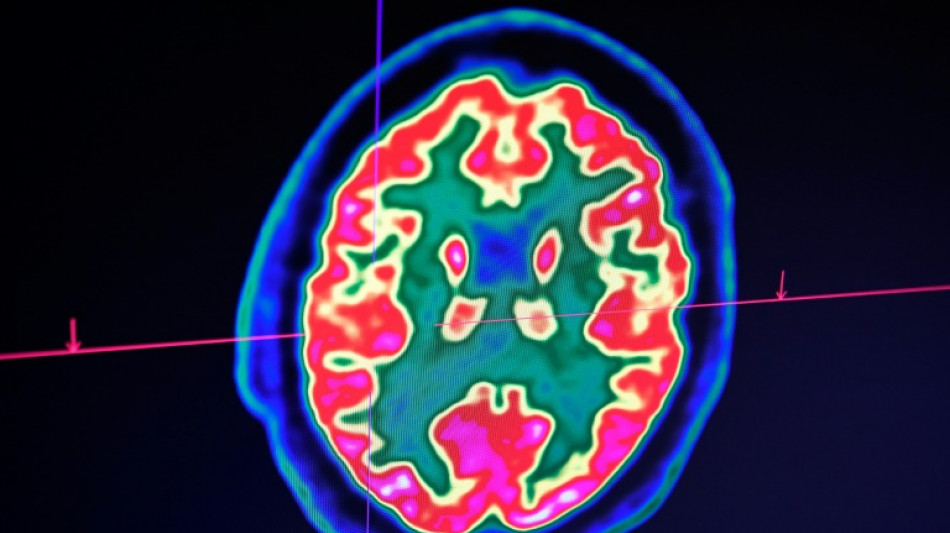

Rare mais fatal, le gliome infiltrant du tronc cérébral est l'une des formes les plus redoutables des cancers du cerveau pédiatriques. Un enfant, pourtant, semble défier les statistiques: sa guérison, unique au monde, suscite aujourd'hui de grands espoirs pour la recherche.

D'emblée, Lucas répond très bien au traitement. "Au fil des IRM, j'ai vu la tumeur complètement disparaître", raconte le Dr Grill, qui n'ose, malgré ces résultats miraculeux, décider d'arrêter le médicament. Jusqu'à ce qu'il comprenne, il y a un an et demi, que l'enfant avait lui-même cessé de le prendre.